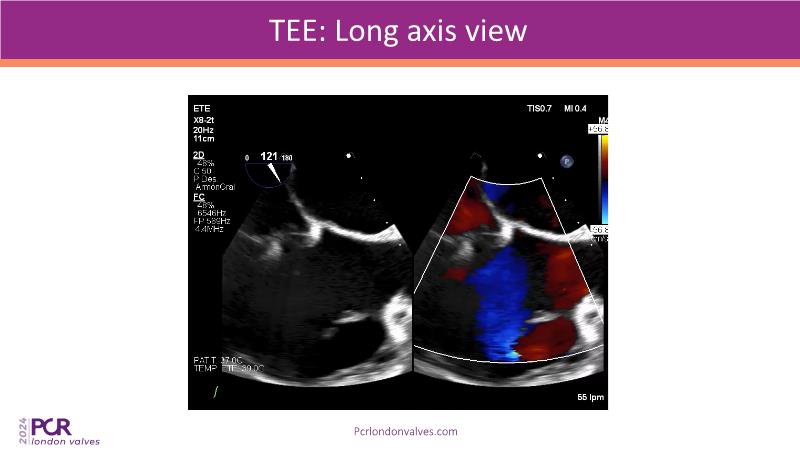

This session examines two compelling cases: a 78-year-old woman with paroxysmal atrial fibrillation, chest trauma, an osteoporotic sternum fracture, and NYHA II exertional dyspnoea, and an 82-year-old man with chronic three-vessel coronary artery disease, bradycardic AF, peripheral arterial disease, spinal stenosis, and chronic kidney disease. Through their study, discover the intricate anatomy of atrioventricular valves, the therapeutic challenges they pose, and the growing significance of transcatheter edge-to-edge repair (TEER) therapies. The discussion also highlights the value of multidisciplinary strategies in managing complex valve diseases effectively.